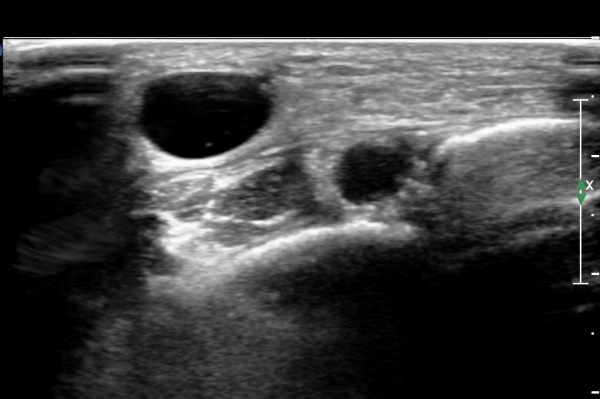

¸»´ÜÀ¸·Î °¥ ¼ö ·Ï ³¶Á¾ÀÌ Ä¿Áø°í õºñ°ñ½Å°æ ¾Ð¹ÚÀº ½ÉÇØÁø´Ù(»çÁø 8).

³¶Á¾À» Á¾´Ü¸éÀ¸·Î °üÂûÇÏ´Ï ³¶Á¾ÀÌ ¸»´Ü °æ°ñºñ°ñ°üÀý¿¡¼ À¯·¡µÊÀÌ È®ÀεȴÙ(»çÁø 9).